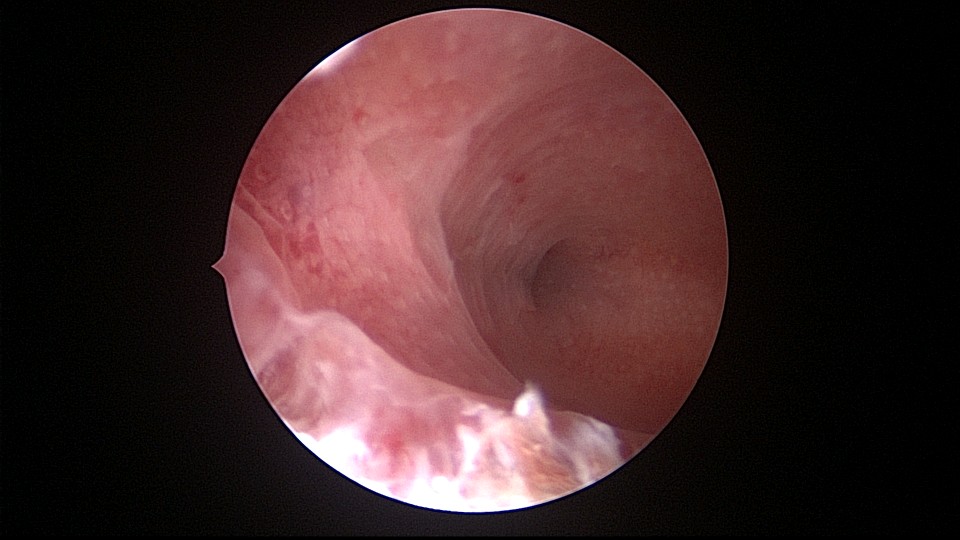

患者34岁,G4P1,顺产1次,继发不孕,宫腔容积小,宫腔粘连。2020年9月宫腔镜探查,见宫腔下段幕状粘连,两侧小孔与宫腔上段相通,形成假的输卵管开口。双极电针切开粘连,宫腔形态恢复正常,显露双侧输卵管正常开口。2020年10月宫腔镜二探取球囊,宫腔形态正常,双侧输卵管开口可见。2021年6月自然妊娠,2022年2月足月剖宫产分娩,2023年5月再次妊娠1次,人流终止妊娠。现39岁,G6P2,顺产1次,剖宫产1次。